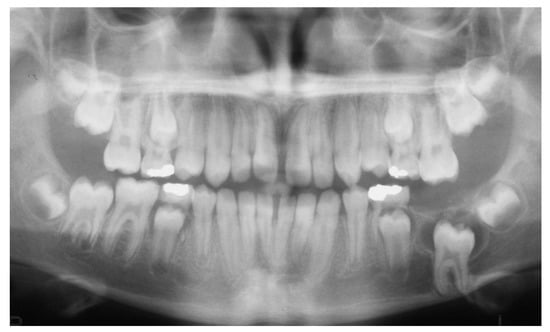

2. Case Presentation